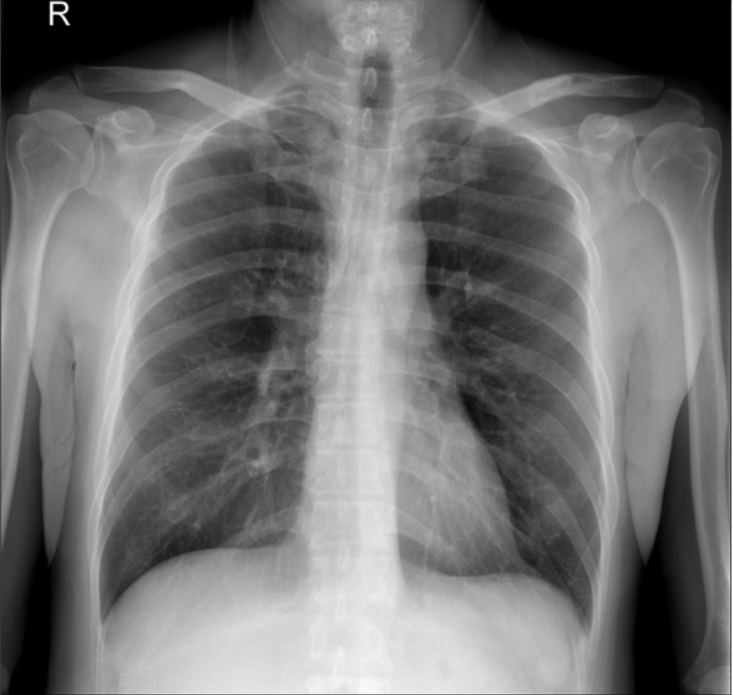

术后立即肩部x线片显示,锁骨骨折切开复位和Knowles针内固定后,肩锁关节(ACJ)明显移位。根据Rockwood分型诊断为V型ACJ脱位